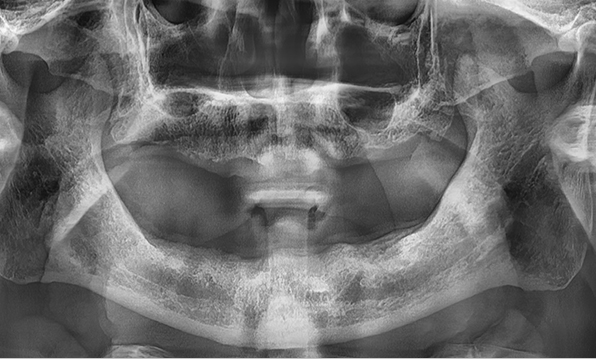

3D 디지털 진단을 통한 체계적인 계획

전체 임플란트는 위턱과 아래턱의 교합, 잇몸뼈의 상태 및

얼굴 변화 등 모든 것을 고려해 식립해야 합니다.

서울더자연치과는 3D 디지털 기술의 정밀 진단을 바탕으로

수술 계획을 세워 수술을 집도합니다.

잇몸뼈가 얇은 상태

잇몸뼈 충분히 이식 후 임플란트 식립

성공을 위한 노하우, 잇몸뼈 재건 기술

전체 임플란트를 해야하는 환자들은

대부분 고령의 환자들로 오랜 틀니 사용

또는 노화로 인해 치조골이

거의 남아있지 않는 경우가 많습니다.

이 때, 치조골 이식을 병행하여 잇몸뼈 재건 후 안정적인 임플란트 식립을 하고 있습니다.

치료기간 : 2021.04.12~2021.09.15